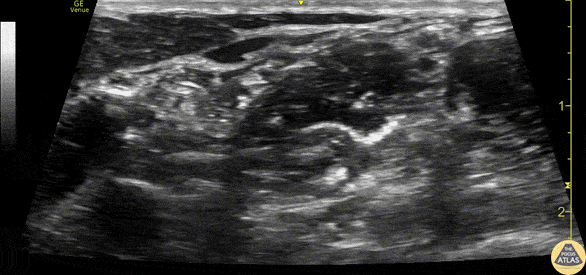

Demonstration of the anatomy of the brachial plexus in the interscalene groove. The C5-7 nerve roots (*) can be seen between the anterior and middle scalene muscles at the right (lateral/posterior) aspect of the image. The posterior edge of the sternocleidomastoid muscle is seen superficial and left of the image. Drs. Sam Paskin-Flerlage, PGY4 and Michael Heffler, PGY3 Denver Health Residency in Emergency Medicine